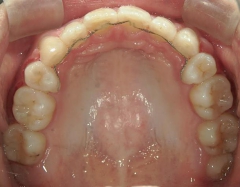

矯正歯科(全顎ワイヤー矯正)治療後

矯正歯科 治療後